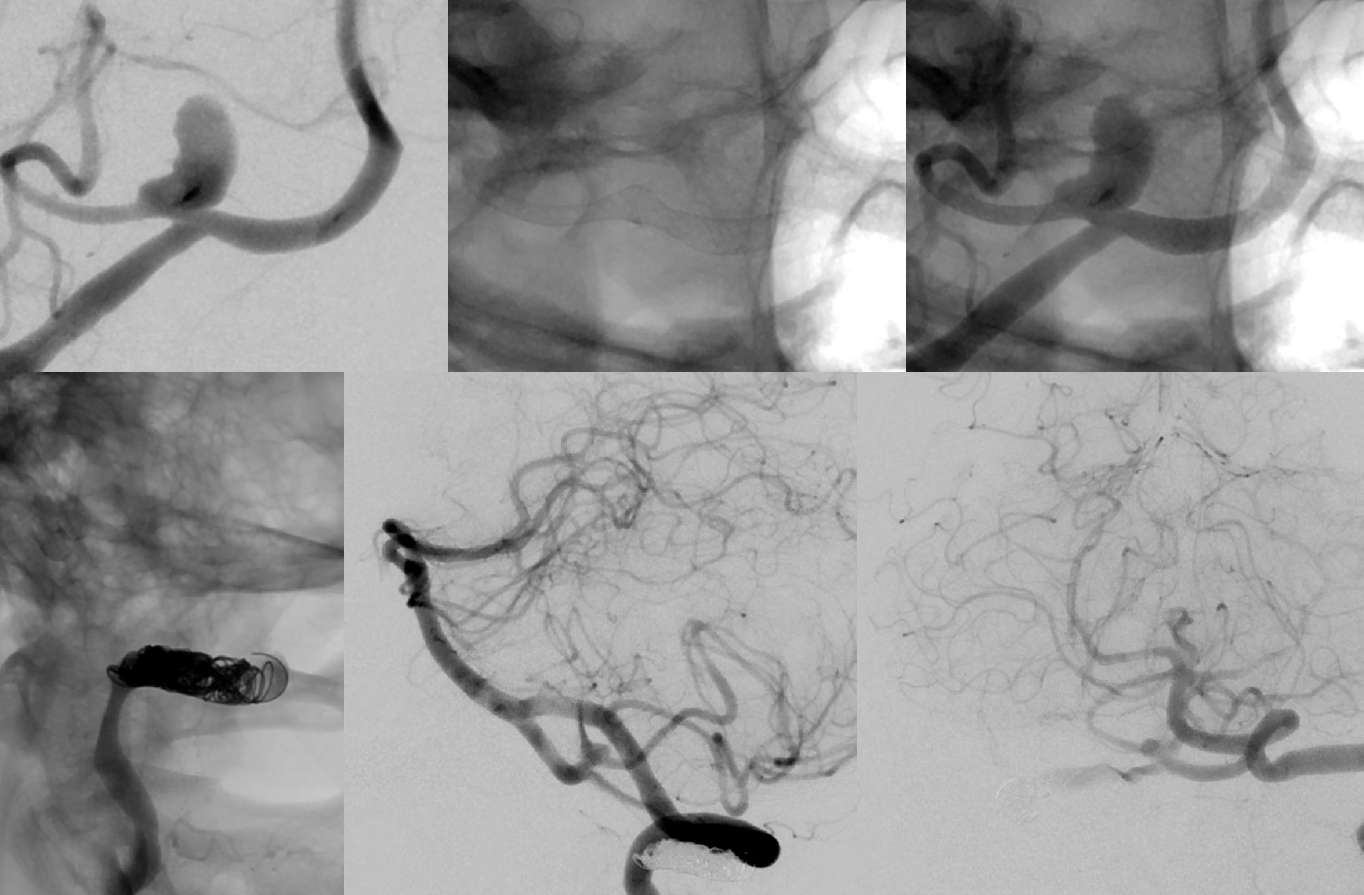

PLan to sacrifice right vert and Pipe across VB junction into PICA.

Could one argue that pipe is not necessary. Possibly. The main point is that this needs aggressive solutions before its too late. Flow reversal is key. What if sac is not enough and mass effect worsens? Take that chance or maximize odds of success with a Pipe? We did what we did

MRI is more important than angio here. A completely thrombosed aneurysm and improved brainstem are sure indications of success

Angio